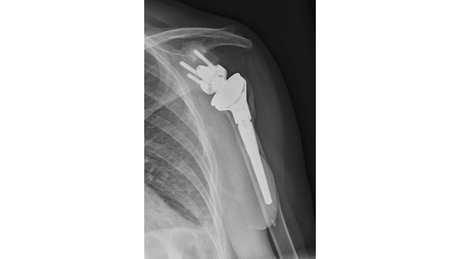

Therapieoption: Implantation einer anatomischen/inversen Schulterprothese

Die Implantation einer Schulterprothese kann bei Arthrose im Schultergelenk, der sogenannten Omarthrose, nötig werden. Hierbei kann man zwei verschiedenen Formen der Arthrose unterscheiden:

In einem Fall ist die Rotatorenmanschette, also die umgebenden Sehnen an der Schulter, welche die Stabilität und Beweglichkeit des Gelenkes gewährleisten, intakt. Der Knorpel ist jedoch aufgebraucht. Bei der Implantation einer Prothese werden die Gelenkpartner ersetzt und deren Form wird beibehalten. Eine sogenannte anatomische Schulterprothese wird implantiert.

Sollte die Rotatorenmanschette, also die umgebenden Sehnen an der Schulter, welche die Stabilität und Beweglichkeit des Gelenkes gewährleisten, nicht mehr intakt sein, dann ist ein anderer Prothesentyp nötig. Hierbei ist die Prothese so aufgebaut, dass sie durch Umkehr der Gelenkformen, die Funktion der fehlenden Sehnen übernimmt. Die flache Pfanne wird sphärisch und der ursprünglich runde Kopf wird als Schale implantiert. Dadurch kann man trotz fehlender Rotatorenmanschette die nötige Stabilität und Beweglichkeit des Schultergelenkes wiederherstellen. Eine sogenannte inverse Schulterprothese wird implantiert.

Sollte bei Ihnen eine Prothesenimplantation durchgeführt werden, sind unter Umständen zuvor verschiedenen bildgebende Verfahren nötig um die korrekte Prothese auswählen zu können.

Bei allen Prothesenformen gibt es verschiedenen Designs. Insgesamt versucht man so knochensparend wie möglich zu operieren. Das bedeutet viel vom eigenen Knochen zu erhalten. Schaftlose Prothesen und kurze Schäfte werden daher bevorzugt. Bei vorbestehender eingeschränkter Knochenqualität kann zur Aufrechterhaltung der Stabilität eine etwas längere Verankerung im Knochen notwendig sein.

Insgesamt ist wichtig, dass man individuell entscheiden muss ob eine Prothese implantiert wird und welche Form der Prothese gewählt wird.

Üblicherweise schließt sich an die Operation eine 5-6 wöchige Nachbehandlung ohne Kraftaufwendung am Arm an. Im Anschluss ist die Prothese gut eingeheilt und man kann mit einer Belastungssteigerung starten. Dies erfolgt üblicherweise im Rahmen eine Rehabilitation, welche bei der Festlegung des Operationstermins, vorab reserviert werden kann.

Auch Revision einer vorhandenen Schulterprothese, die Konversion von anatomischer Prothese auf eine inverse Prothese, partieller Wechsel oder gesamter Wechsel werden angeboten und durchgeführt.